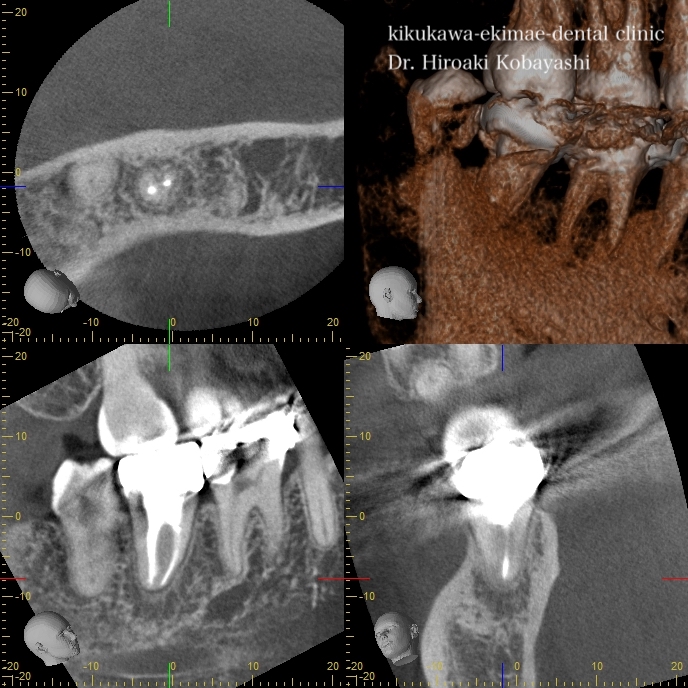

根管治療後の骨の再生

精密根管治療にて細菌を除去し、根の薬を入れた直後はまだ完全な骨の再生は起こりません。

6ヶ月〜1年ほどかけて骨の再生が起こります。適切な時間を確保し、顕微鏡やラバーダムをちゃんと使用した、精密根管治療により根の中の細菌感染がなくなれば後は体が勝手に治してくれます。あとは、被せ物をきちんと入れる事と、セルフケアの徹底にて長期の保存を目標とします。